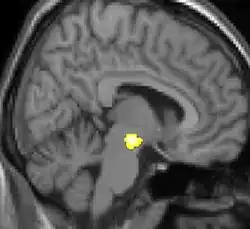

La Morfometría Basada en Vóxel (en inglés, Voxel-Based Morphometry; VBM) es una técnica de análisis en neuroimagen que permite la investigación de diferencias focales en la anatomía del cerebro, usando una aproximación estadística paramétrica mediante la división del cerebro en voxels.[1]

Esta técnica va a provechar la capacidad de la resonancia magnética estructural y así lograr identificar las diferencias de concentración de entre la sustancia gris y sustancia blanca del cerebro las cuales se miden en cada voxel (decenas de miles de pequeñas regiones en varios milímetros cúbicos de tamaño).

Uno de los primeros estudios que utilizaron la técnica VBM y que llamó la atención de los medios de comunicación, fue sobre la estructura de los hipocampos de los taxistas de Londres. El análisis VBM mostró que la parte posterior del hipocampo es más grande en los taxistas de Londres en comparación con sujetos de control, que tenían esta área en promedio más pequeña. Los taxistas de Londres necesitan buenas dotes de orientación espacial para guiarse por el callejero de Londres, y esta habilidad se ha asociado especialmente con el hipocampo.